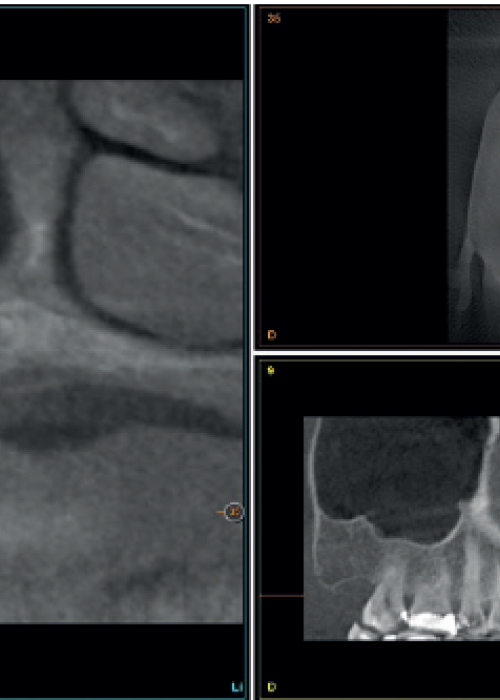

Elevación de seno mediante abordaje transcrestal sin material de relleno con implantes extracortos (5,5 y 6,5 mm). Estudio retrospectivo con un seguimiento de 10 años

Elevación de seno transcrestal con inserción de implantes ultracortos de 4,5 mm de longitud en zonas maxilares posteriores con hueso residual menor o igual a 3 mm de altura

Implantes de 4,5 y 5,5 mm longitud insertados de forma directa en elevación crestal con hueso autólogo unido al Endoret-PRGF en alturas óseas residuales de 2-3 mm: estudio retrospectivo